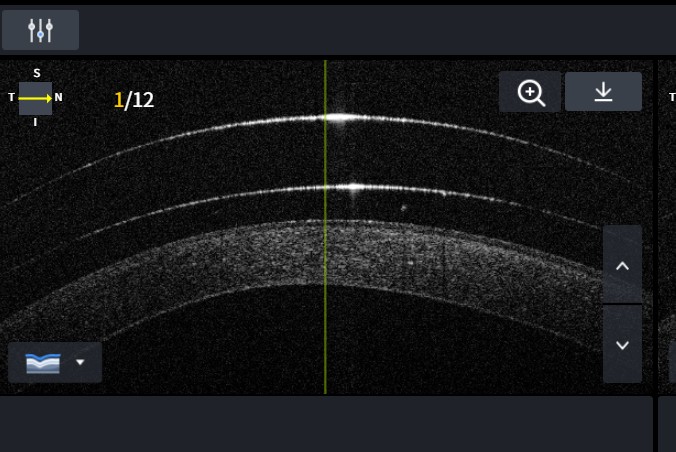

Een indicatieve oogmeting en een uitgebreid onderzoek met de biomicroscoop (spleetlamp) is de eerste stap. De bolling, kromming en afvlakkingen van de oogbol en de sclera worden bepaald. Een topograafmeting geeft direct een indicatie van een onregelmatige cornea, zoals bij keratoconus. Aanvullend wordt een voorsegment-oogscan gebruikt om diepere lagen, zoals de achterzijde van het hoornvlies, te bekijken.

Na ESP-opmeting worden proefscleralenzen geselecteerd en aangebracht. De optometrist beoordeelt via spleetlamp de klaring (vault) boven het hoornvlies, de landing op de sclera en de centering. Aanpassingen worden iteratief doorgevoerd tot een optimale pasvorm is bereikt. Bij medische indicaties wordt samengewerkt met de verwijzend oogarts of specialist.